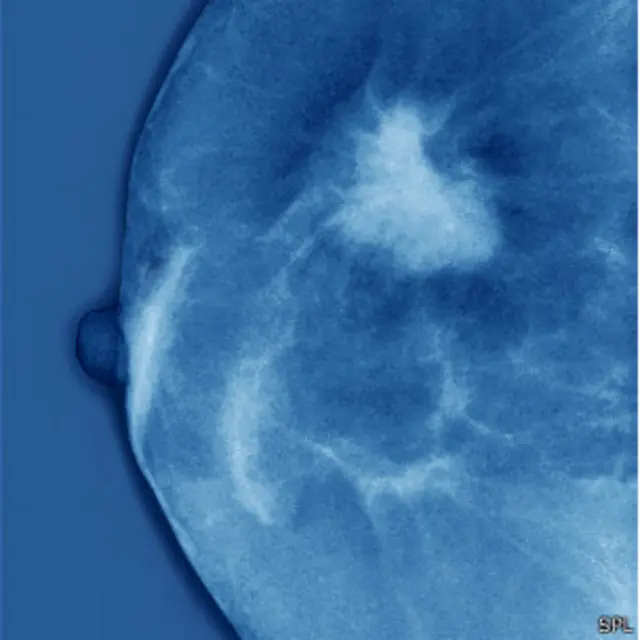

En esencia, el cáncer es una célula en miles de millones que empieza a funcionar mal. En el caso del cáncer de mama, la gran mayoría de las veces esa célula maligna se encuentra en los conductos que llevan leche desde la glándula mamaria hasta al pezón. Pero, ¿por qué allí y no en otra parte? ¿Qué hay en esa zona?

Las células luminares progenitoras se dividen en lo que se llaman células diferenciadas o finales, que a su vez forman el conducto en el pecho. Es en estas células madre donde se origina el cáncer de mama.